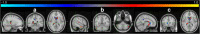

NeAT is a modular, flexible and user-friendly neuroimaging analysis toolbox for modeling linear and nonlinear effects overcoming the limitations of the standard neuroimaging methods which are solely based on linear models. NeAT provides a wide range of statistical and machine learning non-linear methods for model estimation, several metrics based on curve fitting and complexity for model inference and a graphical user interface (GUI) for visualization of results. We illustrate its usefulness on two study cases where non-linear effects have been previously established. Firstly, we study the nonlinear effects of Alzheimer's disease on brain morphology (volume and cortical thickness). Secondly, we analyze the effect of the apolipoprotein APOE-ε4 genotype on brain aging and its interaction with age. NeAT is fully documented and publicly distributed at https://imatge-upc.github.io/neat-tool/ .